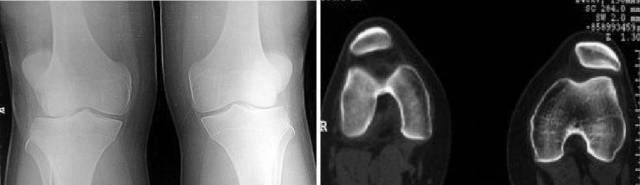

膝关节的牵涉痛,儿童和十几岁的少年,膝关节疼痛的定位不清,没有膝关节外伤史,体重超重,受累髋关节轻度屈曲外旋,被动内旋和伸直受累髋关节可引发疼痛,膝关节检查正常,典型的X线表现为股骨头骨骺移位,临床表现典型但摄片阴性不能排除诊断,此时CT扫描有助于诊断。